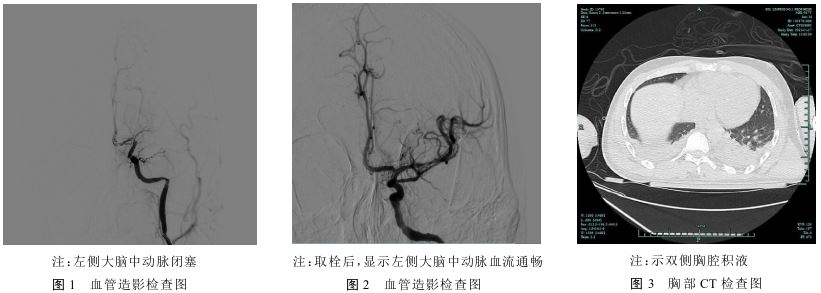

患者男,27岁,因“突发右侧肢体无力伴言语不能4 h”于2022年11月16日被送至杭州市临平区第一人民医院急诊就医。体格检查:血压123/76mmHg(1 mmHg≈0.133 kPa),体质量67 kg,嗜睡,精神软,运动性失语,两侧额纹对称,双侧鼻唇沟基本对称,伸舌不合作;右侧肢体肌力1级,左侧肢体肌力5级,感觉检查不合作,右侧巴氏征阳性,左侧巴氏征阴性,心肺腹及脑膜刺激征查体阴性。予启动脑梗死溶栓治疗流程,头颅CT未见明显出血,脑动脉CT血管造影(CTA)提示:左侧大脑中动脉未见明显显示,闭塞考虑。排除禁忌并取得知情同意后予阿替普酶静脉溶栓,症状未见好转,随即行全脑CTA+急性脑梗死机械取栓术,术中造影示左侧大脑中动脉闭塞,见图1;予支架联合抽吸取栓,取出暗红色血栓,复查造影见左侧大脑中动脉血流通畅,见图2。

患者否认高血压、糖尿病、心脏病等慢性基础病史,否认长期用药史,吸烟史10年,20支/d;饮酒史10年,未戒。入院后实验室检查:D-二聚体1.09 mg/L;血生化:总蛋白32.0 g/L,清蛋白14.0 g/L,三酰甘油1.85 mmol/L,总胆固醇5.4 mmol/L,空腹血糖5.0 mmol/L,低密脂蛋白胆固醇3.37 mmol/L,同型半胱氨酸11.6 mol/L;术前四项、男性肿瘤、血常规+C反应蛋白(CRP)未见明显异常;抗核抗体、PR3/MPOC、c ANCA、p ANCA阴性;尿常规:蛋白质3(+);尿生化:总蛋白(尿)5171.3 mg/L,总蛋白(尿)/肌酐(尿)3 651.593 mg/g,微量白蛋白(尿)916.9 mg/L cr,微量白蛋白(尿)/肌酐(尿)647.0 mg/g cr;免疫球蛋白G 2.88 g/L,尿免疫球蛋白轻链230.00 mg/L,尿免疫球蛋白轻链330.00 mg/L;蛋白浓度(尿)5 220mg/24 h,24 h尿量2 600 ml,尿蛋白定量13 572mg/24 h;磷脂酶A2受体(PLA2R)40 IU/ml,抗肾小球基底膜IgG抗体阴性;影像学检查:彩色多普勒超声显示心包积液,胸腔积液探查:心包少量积液、双侧胸腔积液。胸部CT平扫提示双侧大量胸腔积液伴双肺膨胀不全,见图3。颈部血管彩色多普勒超声:双侧颈总动脉、颈总动脉分叉处、颈内动脉及颈外动脉未见明显异常,双侧锁骨下动脉未见明显异常。双下肢静脉彩色多普勒超声提示血流通畅。